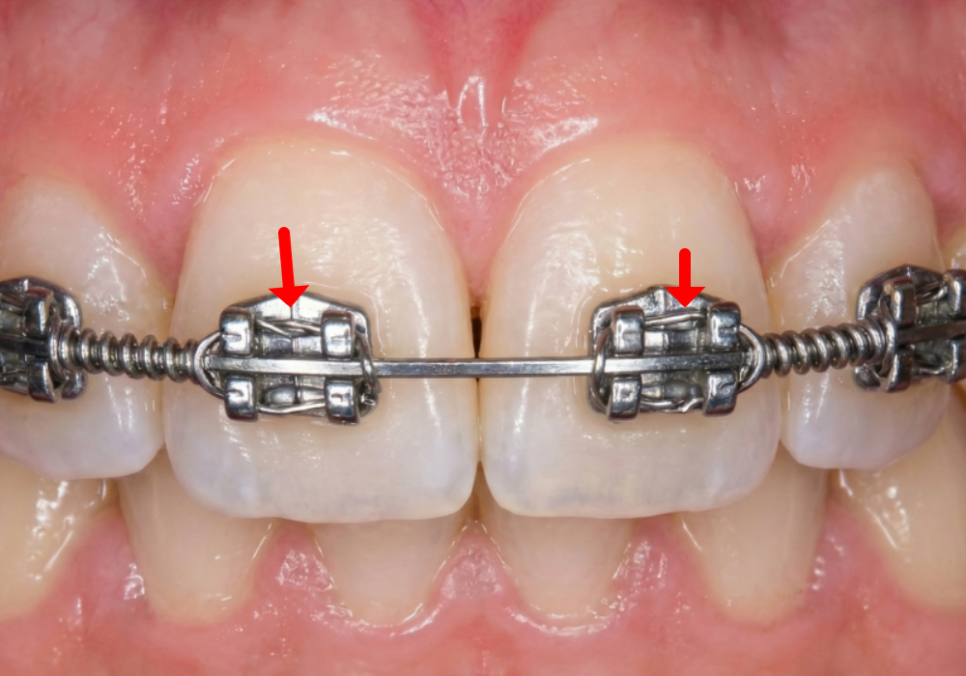

브라켓을 얇은 철사로 묶은 모습 (치아마다 묶어야 했기 때문에 시간이 오래 걸림)

예전 교정 방식은

와이어를 고정하기 위해

고무줄이나 얇은 철사로

일일이 묶어야 했습니다.